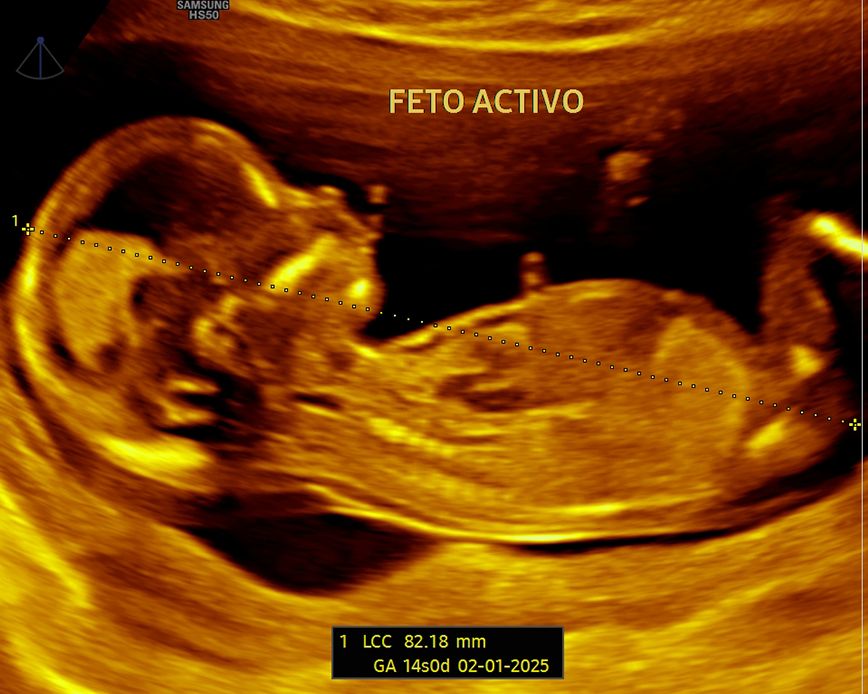

Esta ecografía permite identificar el sexo del bebé con precisión a partir de la semana 12 de gestación. Además, ofrece información sobre el bienestar fetal, la ubicación de la placenta y la cantidad de líquido amniótico, asegurando el monitoreo adecuado del embarazo.

Esta ecografía permite identificar el sexo del bebé con precisión a partir de la semana 16 de gestación. Además, ofrece información sobre el bienestar fetal, la ubicación de la placenta y la cantidad de líquido amniótico, asegurando el monitoreo adecuado del embarazo.